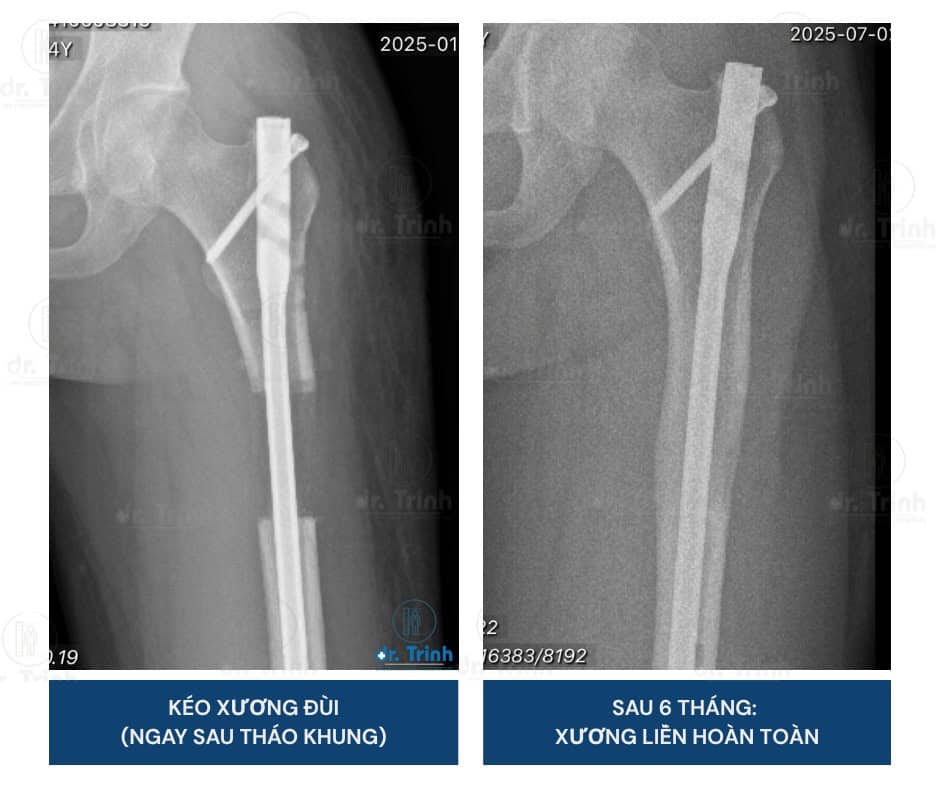

📸 X-quang trong quá trình kéo xương đùi được 2 – 5 – 6 cm

Hình ảnh sau 6 tháng tháo khung kéo dài xương đùi

Chi phí phẫu thuật kéo dài xương đùi phụ thuộc vào phương pháp và thời gian điều trị. Với trường hợp bạn N., chỉ sau 6 tháng, Hình ảnh X-quang mới nhất cho thấy can xương đã liền HOÀN TOÀN và bạn có thể chạy bộ bình thường.